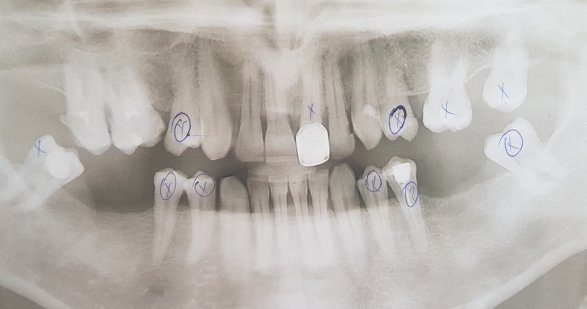

Что делать, подскажите пожалуйста? (1й снимок после первого лечения, 2-й после перелечивания)

Канал зуба на первом снимке запломбирован хорошо, я не вижу там резорцин-формалина, так как он на рентгене контрастен, а на снимке явно видна пломбировка силлером. Боли не понятно с чем связаны. Зачем нужно было выводить материал за верхушку? Это грубое нарушение!